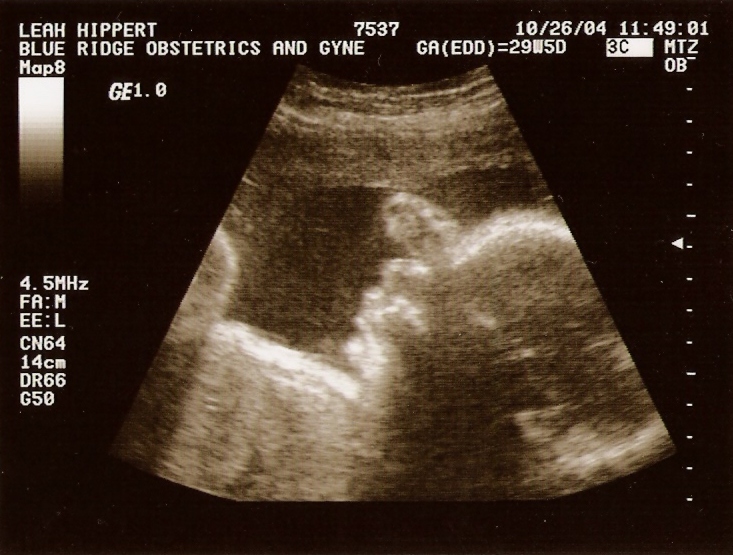

Ultrasound

Taken On October26th 2004   Taken On October26th 2004   Taken On October26th 2004